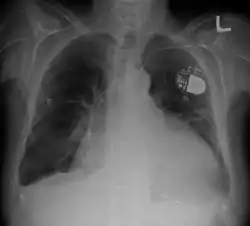

![]() ناظمة قلبية اصطناعية وتضخم القلب يظهران في أشعة سينية للصدر. ناظمة قلبية اصطناعية وتضخم القلب يظهران في أشعة سينية للصدر. | |